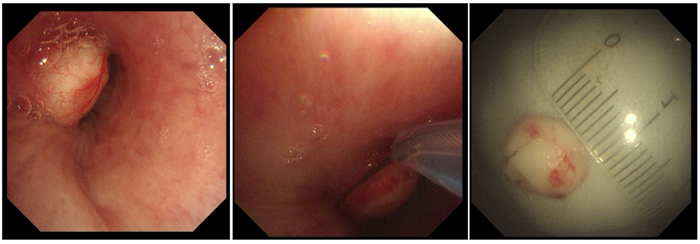

2月15日,由于世倫副院長(zhǎng)親自操作,在狄紅紅主治醫(yī)師、田忠敏護(hù)士長(zhǎng)協(xié)助下,成功為患者行高頻電套扎切除結(jié)節(jié)狀白色腫物。

患者左主支氣管遠(yuǎn)端見(jiàn)結(jié)節(jié)狀白色腫物,表面上有少許表淺血管顯露,基底較寬,堵塞管腔約70%,予以高頻電套扎切除,少許出血,給與局部噴灑腎上腺素溶液止血,標(biāo)本送病理。2月16日病理結(jié)果示:肺錯(cuò)構(gòu)瘤?;颊哂?月16日出院,醫(yī)護(hù)人員就復(fù)診問(wèn)題給予其詳細(xì)的指導(dǎo)。